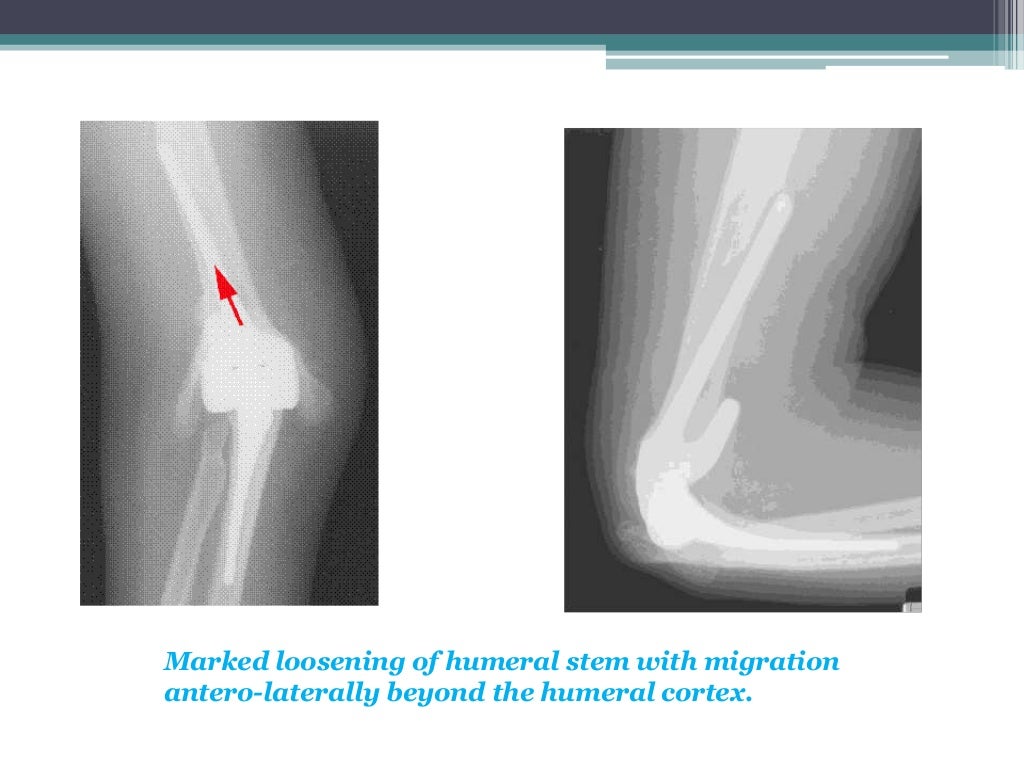

Total elbow arthroplasty What Is A Elbow Arthroplasty elbow replacement is also called elbow arthroplasty or elbow joint replacement. In total elbow replacement surgery, the damaged parts of the humerus and ulna are replaced with artificial components. the aim of the operation is to replace the damaged parts of the elbow joint and with artificial compartments to enable a smoother less painful range of. the. What Is A Elbow Arthroplasty.